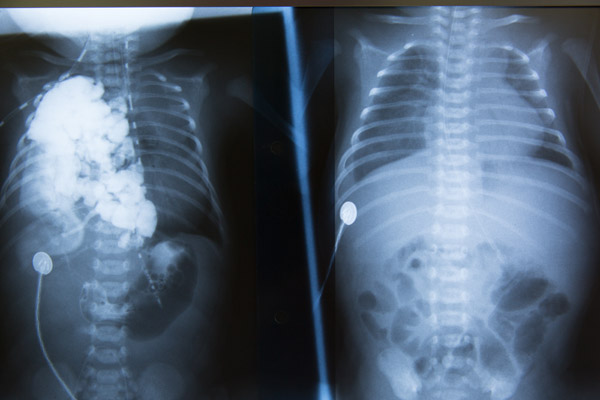

Conform protocolului de evaluare a copiilor diagnosticati cu hernie diafragmatica congenitala, Tudor a fost investigat complet, efectuandu-se o serie de teste, cum ar fi gaze sanguine, analize de sange, ecocardiografie, ecografie abdominala, tranzit baritat, etc. Radiografia pulmonara a evidentiat ca intreg hemitoracele drept era ocupat cu anse intestinale si o portiune din ficat, ceea ce reprezenta un factor de prognostic sever.

„A fost o operatie complexa, din cauza localizarii bresei pe partea dreapta, ceea ce a facut ca abordul sa fie unul dificil. Defectul a fost unul mare, jumatate din ficat si aproape 90% din intestine fiind herniate in torace. Organele migrate au fost repozitionate in abdomen, iar diafragmul a fost reconstruit. Astfel, spatiul creat in torace va permite plamanilor sa continue sa creasca si sa se dezvolte cat mai normal pana la varsta de 8-9 ani.” - a declarat dr. Dan Cristea.